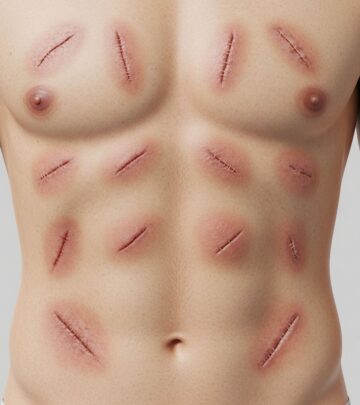

- Surgical Intervention: In severe cases or when conservative measures fail, surgical procedures may be considered to correct muscle imbalances or address structural issues contributing to pes cavus. Surgical options may include soft tissue procedures, bony surgery, and toe surgery.